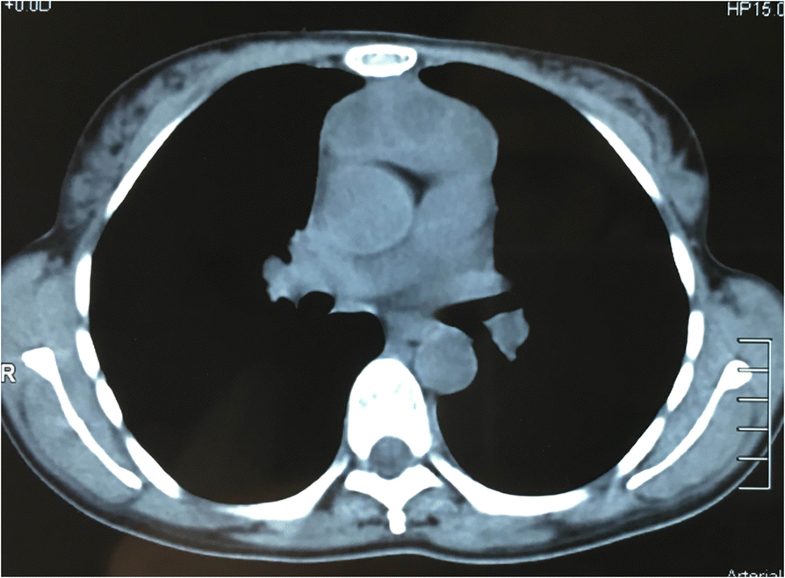

Computed tomography (CT) scan of a thymic cyst. (a) A plain CT scan of Are Thymic Cysts Cancerous Thymic epithelial tumours represent a heterogeneous group of rare thoracic cancers, with reported annual incidence ranging from 1.3 to 3.2 per million [1]. Overall, common symptoms caused by thymic cysts included cough (10.2%), followed by dyspnea (5.6%), retrosternal chest pain (5.6%),. There’s also a much rarer form of thymus gland cancer called thymic carcinoma. Cancer of the thymus gland is. Are Thymic Cysts Cancerous.

Multilocular thymic cyst in a 43yearold woman with primary Sjögren

Idiopathic Multilocular Thymic Cyst CT Features with Clinical and Are Thymic Cysts Cancerous Learn about symptoms, diagnosis, tests and. Hsu ch, chan jk, yin ch, et. There’s also a much rarer form of thymus gland cancer called thymic carcinoma. Thymic cysts are benign lesions that can be congenital or acquired, often asymptomatic and discovered incidentally during imaging. Thymic epithelial tumours are rare and the cause is unknown. They occur when cancer (malignant) cells. Are Thymic Cysts Cancerous.

Idiopathic Multilocular Thymic Cyst CT Features with Clinical and Are Thymic Cysts Cancerous Hsu ch, chan jk, yin ch, et. Thymic tumours are rare, although they are the most common anterior mediastinal tumours in adults. Thymic cysts are benign lesions that can be congenital or acquired, often asymptomatic and discovered incidentally during imaging. Find out about types of thymus cancer (thymoma and thymic carcinoma) with macmillan. Thymic epithelial tumours are rare and the. Are Thymic Cysts Cancerous.